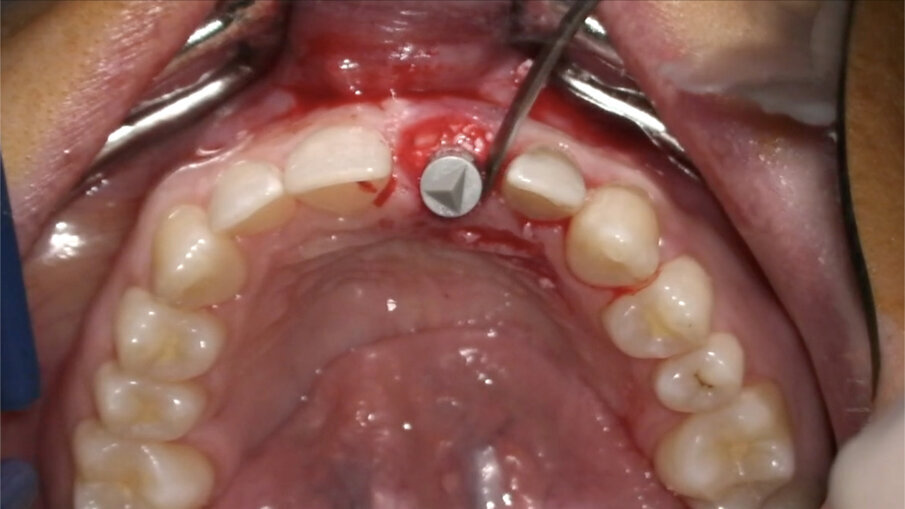

L’impianto (XIVE – Dentsply Sirona) è stato posizionato centralmente con un’inclinazione palatale al fine di evitare che il foro di accesso della vite cadesse sul margine incisale del provvisorio o, ancor peggio, sulla sua superficie vestibolare. Il gap osseo vestibolare è stato riempito con Geistlich Bio-Oss (Geistlich Pharma) (Figg. 16-19).

- Personalizzazione matrice “FIBRO-GIDE”

Geistlich Fibro-Gide (Geistlich Pharma) è una matrice in collagene di origine suina, porosa, riassorbibile e volumetricamente stabile, progettata specificatamente per la rigenerazione e l’aumento dei tessuti molli al fine di evitare il prelievo autologo di tessuto connettivo. Tale matrice, usata in guarigione sommersa, favorisce l’angiogenesi, la formazione di nuovo tessuto connettivo e permette la stabilità volumetrica dei tessuti, ripristinando la corretta ampiezza biologica1-11. In un caso estetico come questo, la matrice va personalizzata e adattata al sito ricevente. Essendo molto stabile e mantenendo il suo volume in fase di guarigione non va, infatti, sovradimensionata per evitare trazioni del lembo e/o volumi eccessivi a guarigione avvenuta; non deve essere inoltre eccessivamente compressa dal lembo in modo che possa mantenere la sua originale struttura reticolare interna. Trattandosi di una matrice particolarmente resistente quando asciutta, suggerisco di modellarla utilizzando una fresa in zirconia a bassi giri (KOMET): in tal modo, infatti, si riesce a modellarla in modo preciso, evitando comunque il surriscaldamento e la denaturazione del collagene mantenendo le sue caratteristiche strutturali inalterate (Figg. 20, 21).

- Posizionamento della matrice e sutura

La matrice va posizionata nella tasca mucosa creata in precedenza (Fig. 22). Nel caso in cui siano state eseguite incisioni, i tessuti molli devono essere ermeticamente suturati sopra di essa, mentre, nel caso opposto, deve essere delicatamente inserita in modo tale da sommergerla completamente.

Fig. 16_Inserimento dell’impianto Xive FX 3.8.

Fig. 17_Posizione corretta dell’impianto post-estrattivo.

Fig. 18_Posizionamento del biomateriale.

Fig. 19_Gestione del biomateriale.

Fig. 20_Personalizzazione della matrice collagene.

Fig. 21_Matrice customizzata.

Fig. 22_Posizionamento della matrice in collagene.